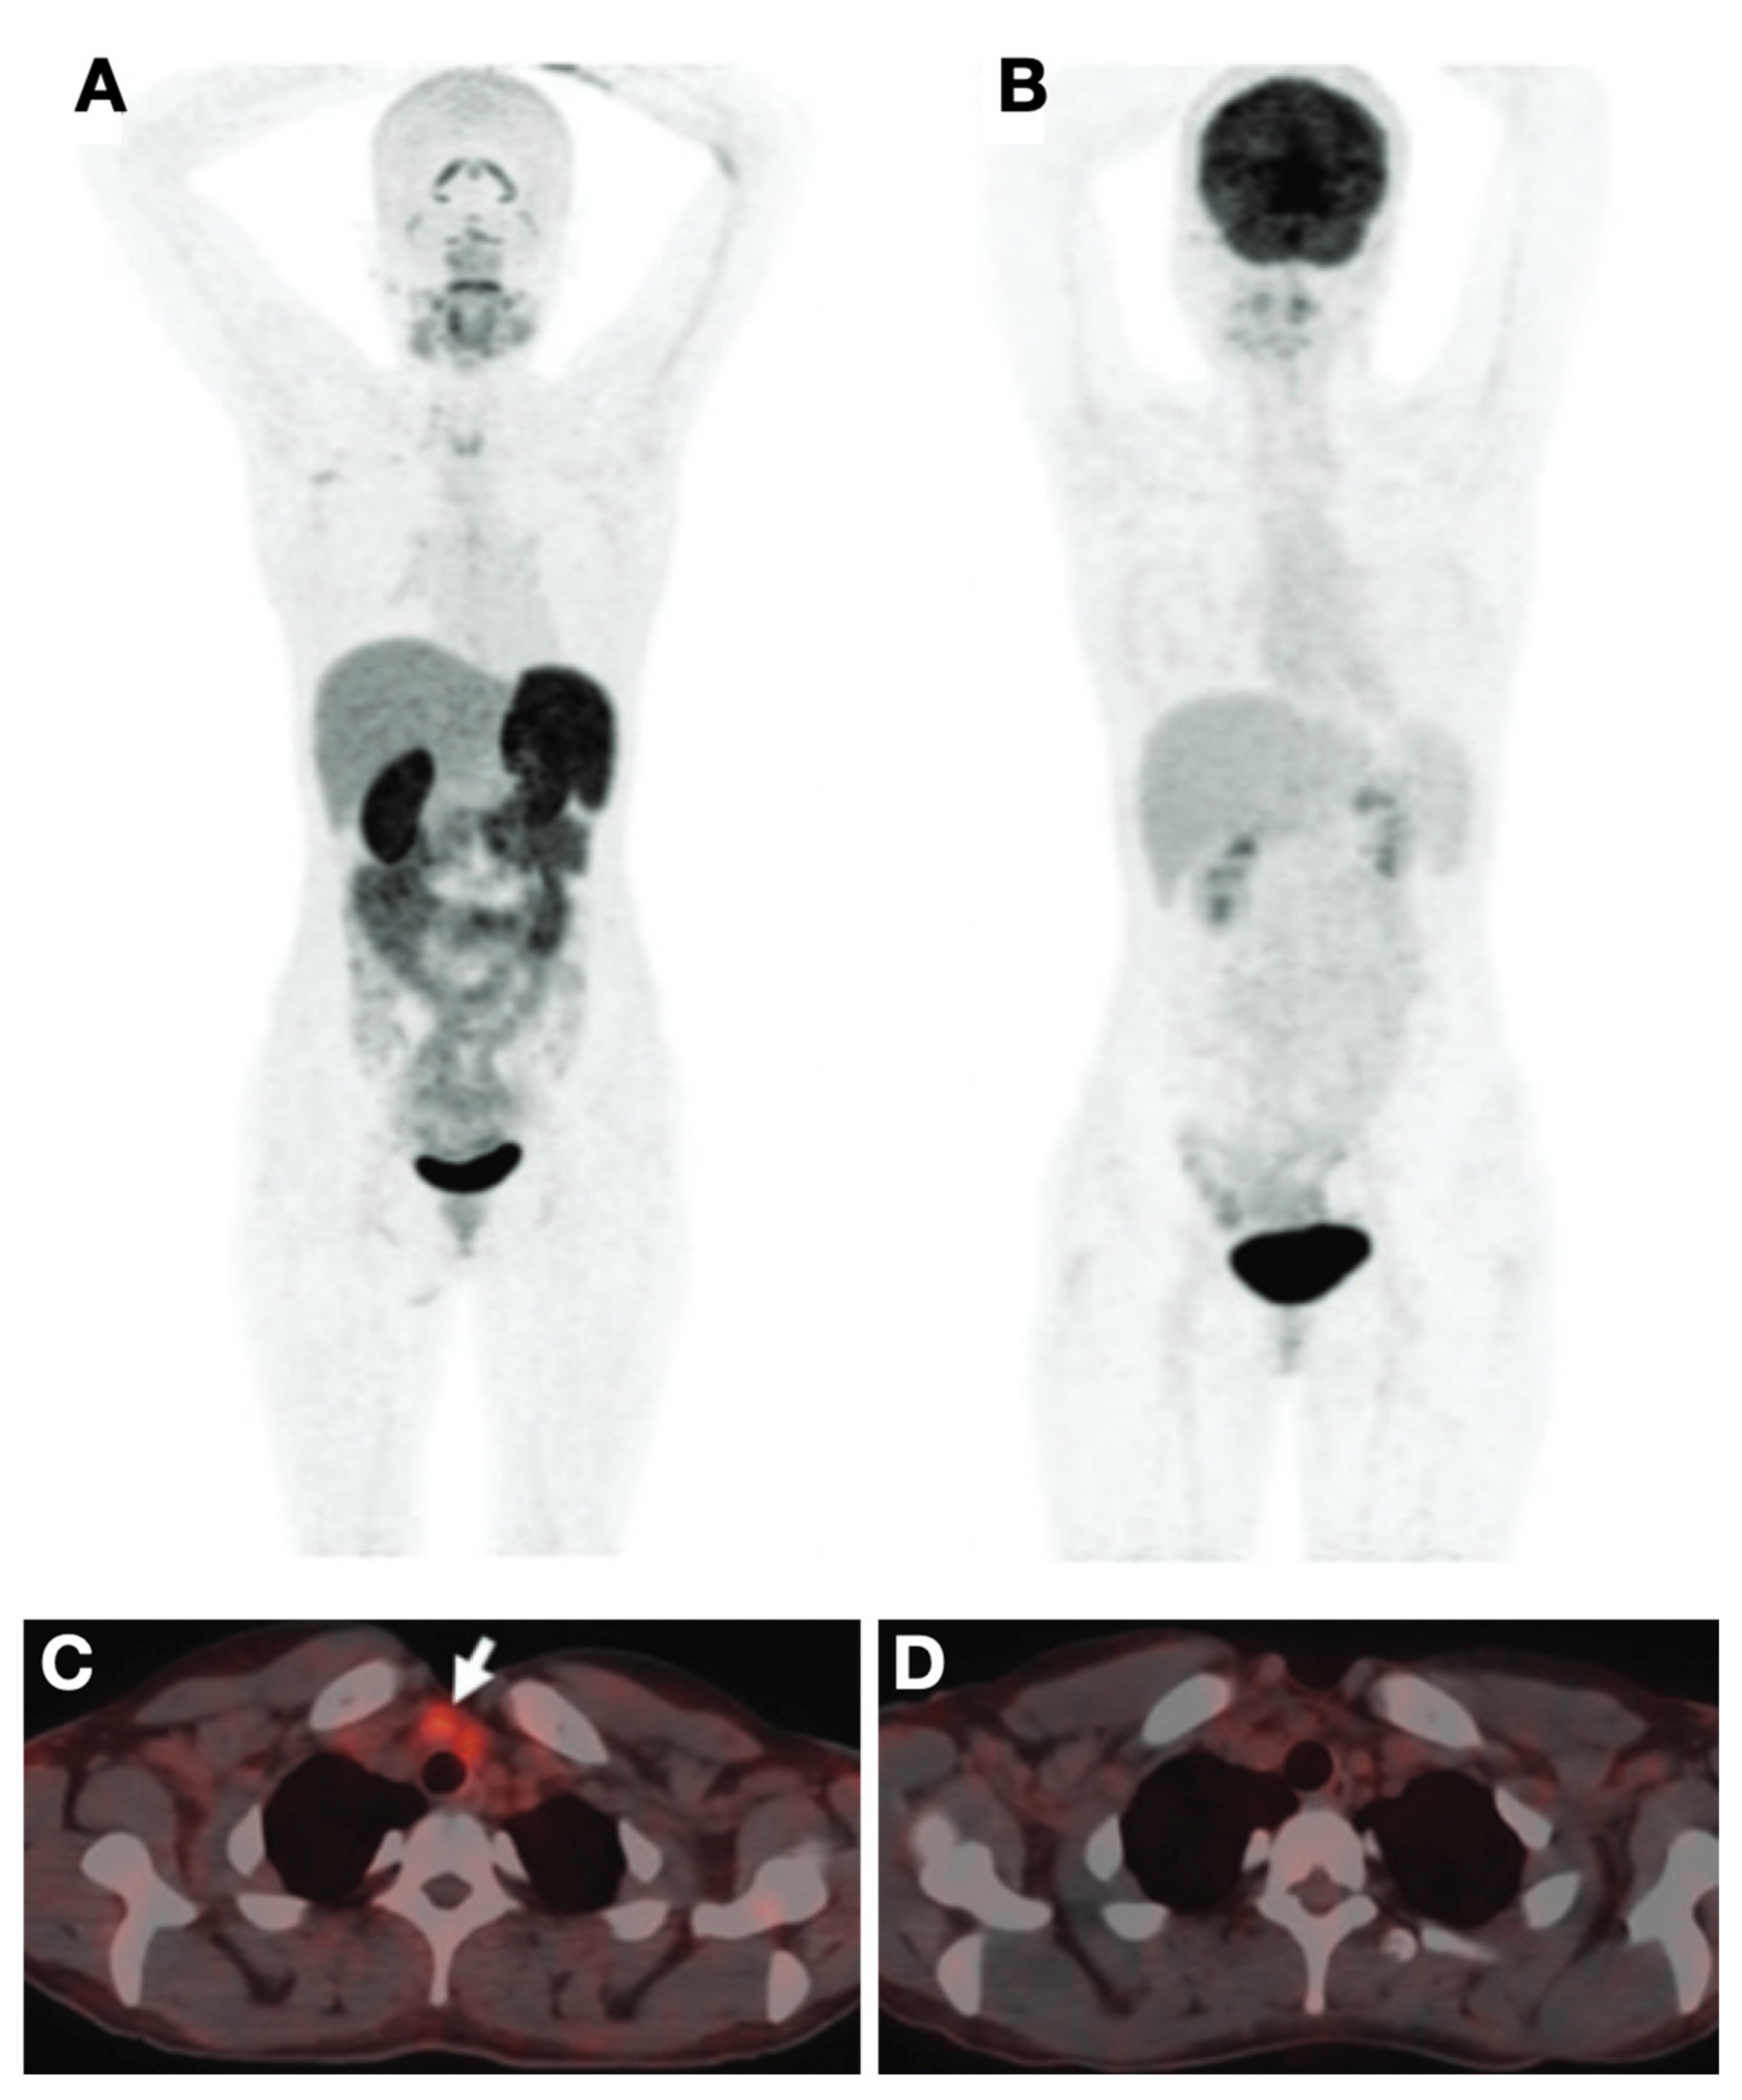

- Ho, A.L.; Grewal, R.K.; Leboeuf, R.; Sherman, E.J.; Pfister, D.G.; Deandreis, D.; Pentlow, K.S.; Zanzonico, P.B.; Haque, S.; Gavane, S.; et al. Selumetinib-Enhanced Radioiodine Uptake in Advanced Thyroid Cancer. N. Engl. J. Med. 2013, 368, 623–632. [Google Scholar] [CrossRef]

- Dunn, L.A.; Sherman, E.J.; Baxi, S.S.; Tchekmedyian, V.; Grewal, R.K.; Larson, S.M.; Pentlow, K.S.; Haque, S.; Tuttle, R.M.; Sabra, M.M.; et al. Vemurafenib Redifferentiation of BRAF Mutant, RAI-Refractory Thyroid Cancers. J. Clin. Endocrinol. Metab. 2018, 104, 1417–1428. [Google Scholar] [CrossRef]